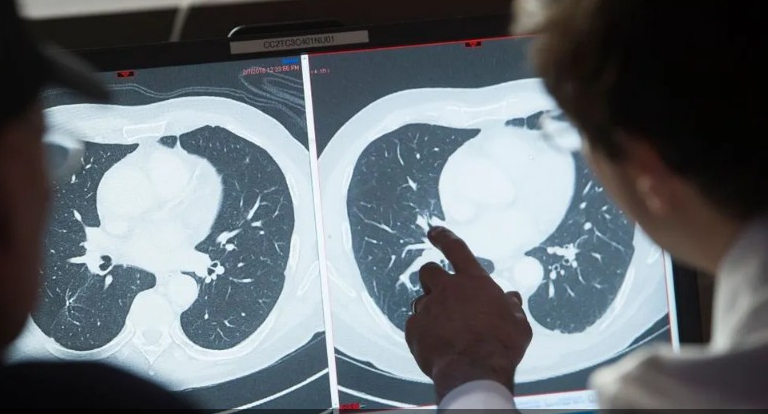

عندما انطلقت رحلة الفضاء "أكسيوم 3" من مركز كينيدي للفضاء في كيب كانافيرال، بولاية فلوريدا الأميركية، في 18 يناير، متجهة إلى محطة الفضاء الدولية، أخذت معها 4 عضيات ورم مصغرة تم إنتاجها من خلايا السرطان لمرضى، والتي تمت زراعتها في المختبر من قبل العلماء في جامعة كاليفورنيا سان دييغو.

عندما يتطور السرطان تحت الضغط، فإن ذلك يرجع إلى جين الاستنساخ الذي يتم تشغيله، والمعروف باسم ADAR1، وفقا لجاميسون. وفي مهمات سابقة، لاحظ فريقها أن الأورام الصغيرة التي تم إرسالها إلى الفضاء قامت بتنشيط الجين قبل أن يتضاعف حجمها ثلاث مرات خلال 10 أيام فقط، وهو معدل نمو أسرع بكثير مما شوهد على الأرض. وكشفت الاختبارات الإضافية أن ADAR1 "انتشر بشكل كبير" في الأورام الفضائية حيث كان ينمو بسرعة مزعجة وغير مقيدة.

في مهمة أكسيوم الأخيرة، أرسل فريق جاميسون أوراما صغيرة تم علاجها بنوعين من الأدوية المضادة للسرطان التي تمنع ADAR1 بطرق مختلفة. وشملت الأدوية عقار فيدراتينيب، الذي تمت الموافقة عليه بالفعل من قبل إدارة الغذاء والدواء الأمريكية لعلاج سرطانات الدم، ولكن ليس الكتل الصلبة.

وبدأ فريق جاميسون العمل بحماس على عقار تجريبي يُدعى ريبسينيب rebecsinib الذي يمنع تنشيط ADAR1 بطريقة مختلفة، عن طريق منعه من إنتاج البروتينات الخبيثة. عندما تم إطلاق أكسيوم 3 الشهر الماضي، كان يتم علاج أورام سرطان الثدي الصغيرة بالخليط الجديد. حتى الآن، وجد الباحثون أنه يمنع نمو السرطان بشكل ملحوظ، بل إنه أكثر فعالية من فيدراتينيب.